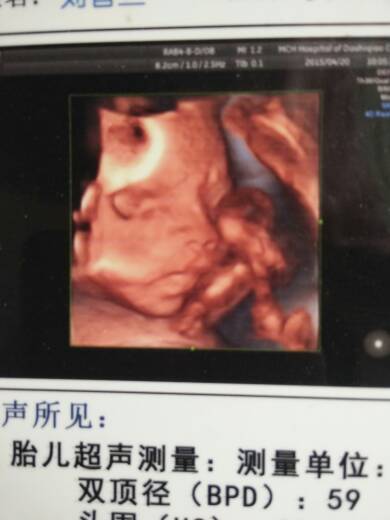

宝妈们,帮我看看我照的4维照片,宝宝是男是女! 宝妈们,帮我看看我照的4维照片,宝宝是男是女! 点击展开 为我儿子攒金币 2015-05-26 08:38 为您推荐: 其他回答 看不出... 笑看人生_XEts 2015-05-26 11:48 祝宝妈好孕 131*****553_2y6x 2015-05-26 09:26 祝宝妈好运 大大怪将军。。 2015-05-26 08:57 爸爸智商高就是生女儿,妈妈智商高就是生男孩 我抠抠是16694180 2015-05-26 08:57 看不出来的宝宝健康比什么都好 星星! 2015-05-26 08:50 加载更多 相关问题 宝妈们有3维照片吗 发张看看 我36岁农立9月怀孕 宝妈帮算是男是女 拜托有经验的帮我看看,现在能看到是男是女吗?还有宝宝有什么不好吗?看不懂这个b超单啊!